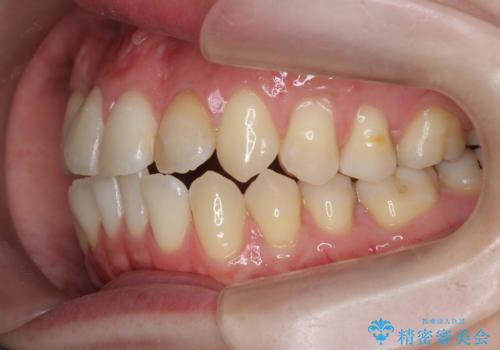

引っ込んだ前歯を並べたい マウスピースと部分ワイヤーのコンビネーション矯正

- 引っ込んで生えてしまっている前歯を並べたい、と矯正治療を希望され来院されました。

まずマウスピース矯正インビザラインシステムで、引っ込んだ歯が並ぶためのスペースを作ったのち、部分ワイヤー矯正を行い短期間での配列を計画します。

このように前歯の部分ワイヤーは引っ込んでしまった前歯や がたつきを素早く改善することができます。